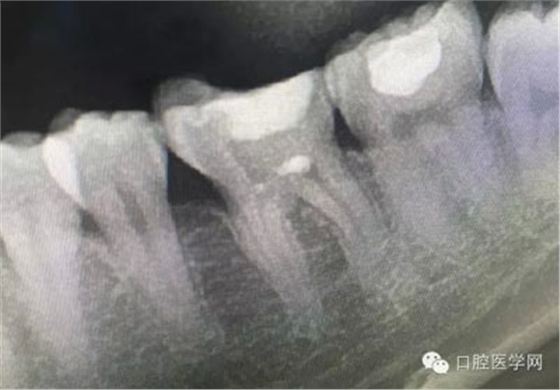

這是一例外院樹脂修復(fù)后十個(gè)月出現(xiàn)牙髓炎癥狀的患者。遇到這樣子的患者大家會(huì)怎么做,證明選擇,還有就是可做可不做治療的如何去平衡。